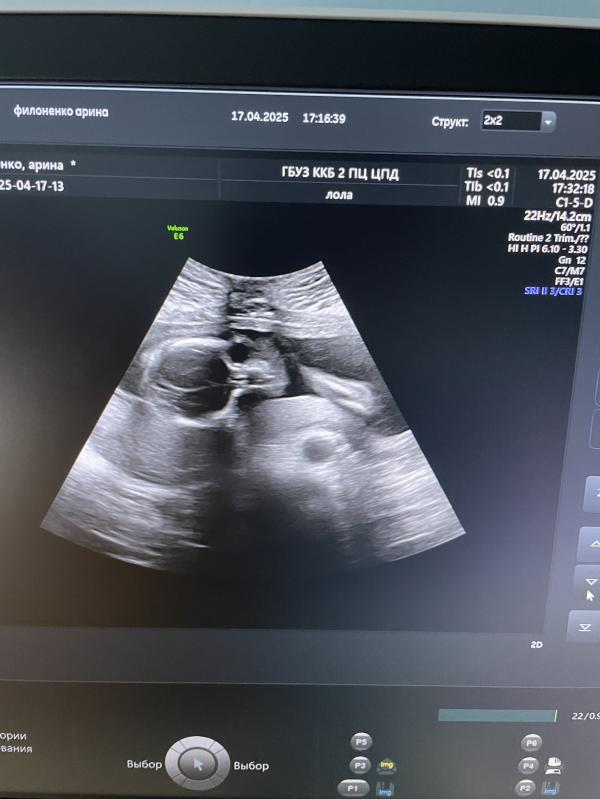

Второй скрининг)

На этот раз сходила на него в свою жк. На удивление врач узи оказалась очень хорошая, Лола Мария Алексеевна 🫶 Постоянно все комментировала, в конце показала снимки и разрешила пофоткать. Кто ходит в 5 жк, от души рекомендую)

У малышарика все хорошо, чуть отстает от срока по месячным (на 2 дня) - поставили 20+3, весит уже 360 грамм. Подтвердили мальчика 😁

Ну а у меня гипертонус, все как обычно, ничего нового… 🫠 Зато плацента чуть поднялась, в прошлый раз перекрывала зев 👍